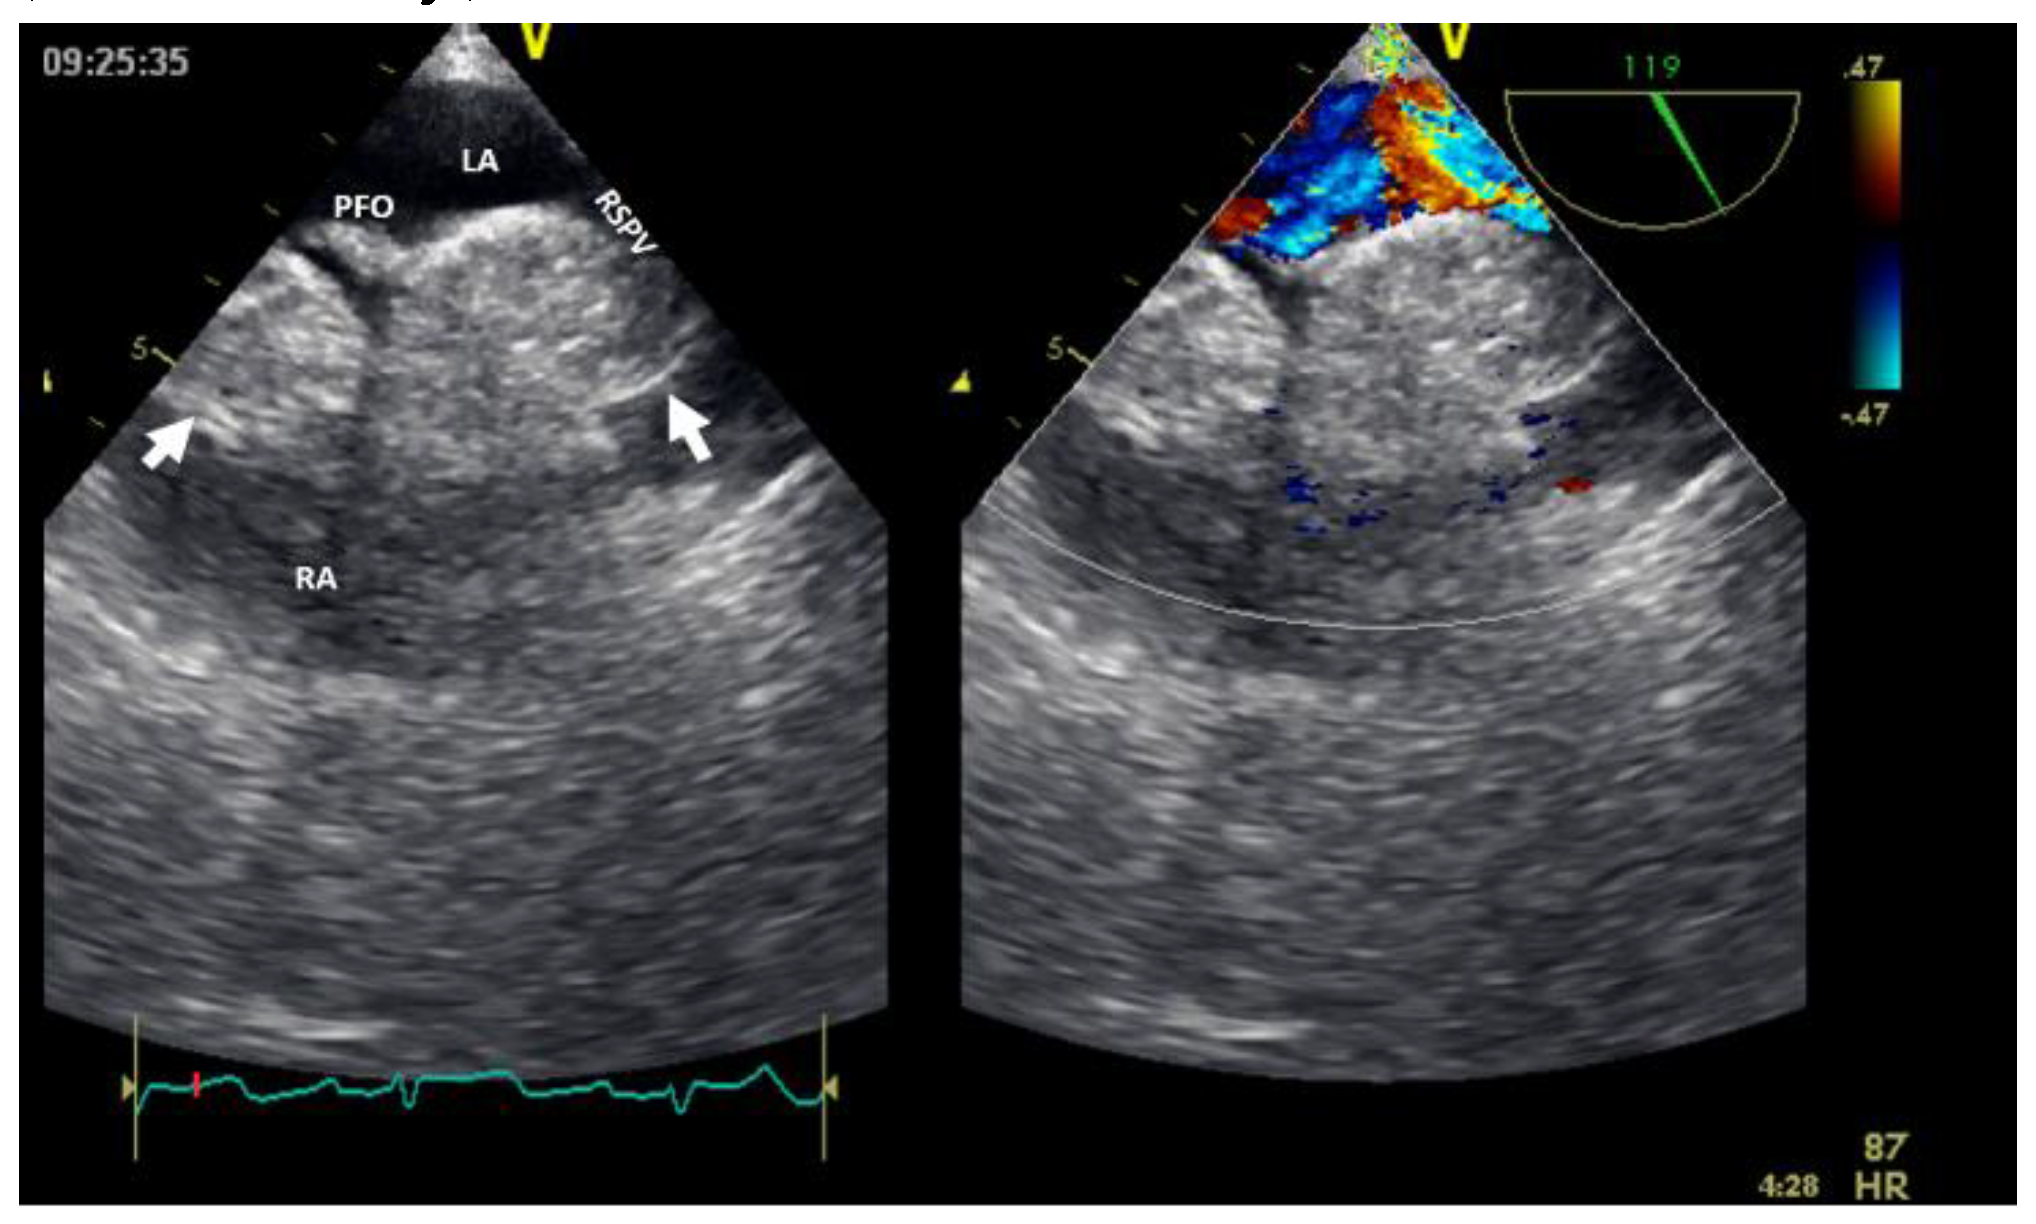

Figure 7. Bi-dimensional transesophageal echocardiography with color Doppler (high transesophageal view at 119°) showing two tumors at the level of interatrial septum with compression on right superior pulmonary vein (right image). LA, left atrium; LV, left ventricle; PFO, permeable foramen oval; RA, right atrium; RSPV, right superior pulmonary vein.

Cardiac lipoma, one of the right heart tumors types, is a very rare primary tumor, without evidence of malignant transformation. Among benign cardiac tumors, lipomas seem to have an incidence between 2.9-8% [4]; could be within the cardiac chamber (about 53%), encompassing all three layers of the cardiac wall (the endocardium, the myocardium in almost 11% of cases, or the pericardium in about 32% of cases) [8]. Cardiac lipomas within the cardiac chamber are usually, smaller than, those within the pericardium. Multimodal noninvasive imaging is important in diagnosis (especially CMR), follow-up, and management of these tumors. In the literature, there are many case reports with right atrial lipomas and fewer with right ventricle lipomas [8]; more than 90% of these patients underwent surgical resection [4,9]. However, this could fail if there is an infiltrative growth into the myocardium. The confirmation of cardiac lipomas by anatomopathological exam is mandatory. Lipomatous hyperplasia or hypertrophy of the myocardium interatrial septum, which is not considered true cardiac lipoma, could be an obstacle to the transseptal puncture in patients undergoing an ablation procedure (Figure 7). Cardiac magnetic resonance can facilitate a differential diagnosis with liposarcoma before resection (if necessary).